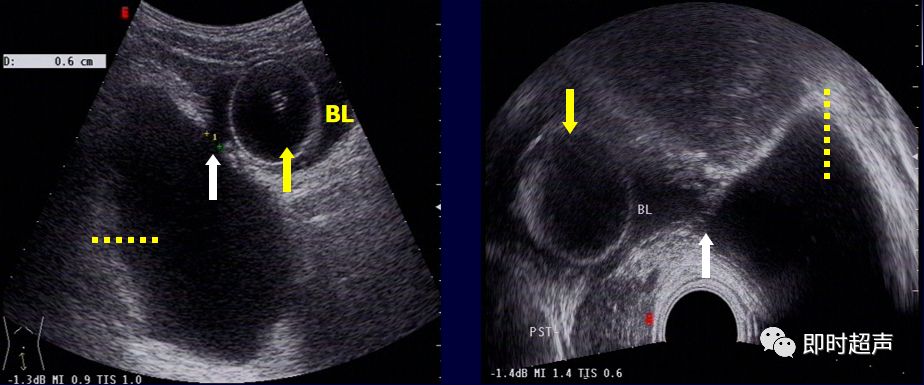

膀胱无回声液性暗区内出现团状强回声,后方伴声影,当体位改变时随体位移动。

膀胱结石:无回声暗区内团状强回声(箭头),后方伴声影(黄箭头)当体位改变时随体位移动

四、膀胱憩室

临床与病理:

- 膀胱憩室是指膀胱壁自分离的逼尿肌之间向外呈袋状膨出而形成的囊状物。

- 其与膀胱内腔之间有孔道相通,称为憩室口,多发生于膀胱三角区周围。

超声表现:

- 膀胱的侧方、后方或某一部位处可见一类圆形的无回声液性暗区

- 壁薄光滑,颇似囊肿,常为单发,可多发

- 排尿前后憩室腔大小随膀胱容量多少而改变

- 可寻找憩室与膀胱之间的通道-憩室口

单发 多发

D:憩室 憩室口(箭头所示)